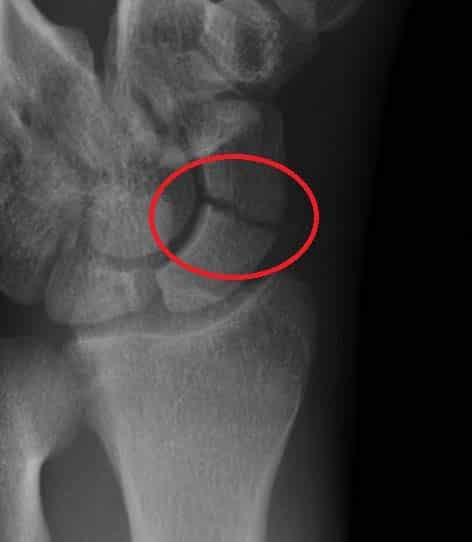

The wrist joint (also known as the radiocarpal joint) is an articulation between the radius and the carpal bones of the hand. It is condyloid-type synovial joint which marks the area of transition between the forearm and the hand. In this article, we shall look at the anatomy of the wrist joint – its structure, neurovasculature and clinical correlations. Pro Feature - 3D Model You've Discovered a Pro Feature Access our 3D Model Library Explore, cut, dissect, annotate and manipulate our 3D models to visualise anatomy in a dynamic, interactive way. Learn More Anatomical Structure Articulating Surfaces The wrist joint is formed by an articulation between: Distal end of the radius and the articular disk. Proximal row of the carpal bones (except the pisiform). Together, the carpal bones form a convex surface, which fits into the concave shape of the radius and articular disk. The ulna is prevented from articulating with the carpal bones by the presence of a fibrocartilaginous ligament, the articular disk. Instead, the ulna articulates with the radius just proximal to the wrist – at the distal radioulnar joint. By TeachMeSeries Ltd (2025) Fig 1Articular surfaces of the wrist joint. Joint Capsule The joint capsule of the wrist joint attaches to the radius, ulna and the proximal row of the carpal bones. It is lined internally by a synovial membrane, which produces synovial fluid to reduce friction between the articulating structures. Ligaments There are four main ligaments located at the wrist joint: Palmar radiocarpal – located on the palmar (anterior) side of the joint. It passes from the radius to both rows of carpal bones. Its function, apart from increasing stability, is to ensure that the hand follows the forearm during supination. Dorsal radiocarpal – Found on the dorsum (posterior) side of the hand. It passes from the radius to both rows of carpal bones. It contributes to the stability of the wrist, but also ensures that the hand follows the forearm during pronation. Ulnar collateral – Runs from the ulnar styloid process to the triquetrum and pisiform. It acts to prevent excessive radial (lateral) deviation of the hand. Radial collateral – Runs from the radial styloid process to the scaphoid and trapezium. It acts to prevent excessive ulnar (medial) deviation of the hand. By TeachMeSeries Ltd (2025) Fig 2Palmar view of the ligaments of the wrist joint. Movements The wrist is an ellipsoidal (condyloid) type synovial joint, allowing for movement along two axes. This means that flexion, extension, adduction and abduction can all occur at the wrist joint. All the movements of the wrist are performed by the muscles of the forearm. Flexion – Produced mainly by the flexor carpi ulnaris, flexor carpi radialis, with assistance from the flexor digitorum superficialis. Extension – Produced mainly by the extensor carpi radialis longus and brevis, and extensor carpi ulnaris, with assistance from the extensor digitorum. Adduction – Produced by the extensor carpi ulnaris and flexor carpi ulnaris Abduction – Produced by the abductor pollicis longus, flexor carpi radialis, extensor carpi radialis longus and brevis. Mobility and Stability The wrist joint is a highly mobile joint to allow the hand to move in several directions. Because of this, the wrist joint is prone to injury. The wrist joint does maintain some stability due to intrinsic and extrinsic ligaments. Intrinsic carpal ligaments, the tiny ligaments between the carpal bones, are short ligaments that provide stability but are easily damaged with excessive force or twisting due to their small size. The extrinsic ligaments, which include the palmar/dorsal radiocarpal ligaments and the radial and ulnar collateral ligaments are stronger and stabilise from the radius and ulna to the carpal bones of the wrist. They are discussed above in further detail. Blood Supply The wrist joint receives blood from branches of the dorsal and palmar carpal arches, which are derived from the ulnar and radial arteries (for more information, see Blood Supply to the Upper Limb) Innervation Innervation to the wrist is delivered by branches of three nerves: Median nerve – Anterior interosseous branch. Radial nerve – Posterior interosseous branch. Ulnar nerve – deep and dorsal branches. Clinical Relevance Injuries to the Wrist Joint Scaphoid Fracture The scaphoid bone of the hand is the most commonly fractured carpal bone – typically by falling on an oustretched hand (FOOSH). In a fracture of the scaphoid, the characteristic clinical feature is pain and tenderness in the anatomical snuffbox. The scaphoid is at particular risk of avascular necrosis after fracture because of its so-called ‘retrograde blood supply’ which enters at its distal end. This means that a fracture to the middle (or ‘waist’) of the scaphoid may interrupt the blood supply to the proximal part of the scaphoid bone rendering it avascular. Patients with a missed scaphoid fracture are likely to develop osteoarthritis of the wrist in later life. By Gilo1969 (Own work) [CC-BY-SA-3.0], via Wikimedia Commons Fig 3Radiograph of a scaphoid fracture. Adapted from work by Iiibalesiii [CC BY-SA 4.0] Fig 4The blood supply to the scaphoid bone runs from distal to proximal. Anterior Dislocation of the Lunate This can occur by falling on a dorsiflexed wrist. The lunate is forced anteriorly, and compresses the carpal tunnel, causing the symptoms of carpal tunnel syndrome. This manifests clinically as paraesthesia in the sensory distribution of the median nerve and weakness of thenar muscles. The lunate can also undergo avascular necrosis, so immediate clinical attention to the fracture is needed. Colles’ Fracture The Colles’ fracture is the most common fracture involving the wrist, caused by falling onto an outstretched hand. The radius fractures, with the distal fragment being displaced posteriorly. The ulnar styloid process can also be damaged, and is avulsed in the majority of cases. This clinical condition produces what is known as the ‘dinner fork deformity’. Do you think you’re ready? Take the quiz below Pro Feature - Quiz The Wrist Joint Question 1 of 3 Submitting... Skip Next Rate question: You scored 0% Skipped: 0/3 1800 More Questions Available Upgrade to TeachMeAnatomy Pro Challenge yourself with over 1800 multiple-choice questions to reinforce learning Learn More Rate This Article